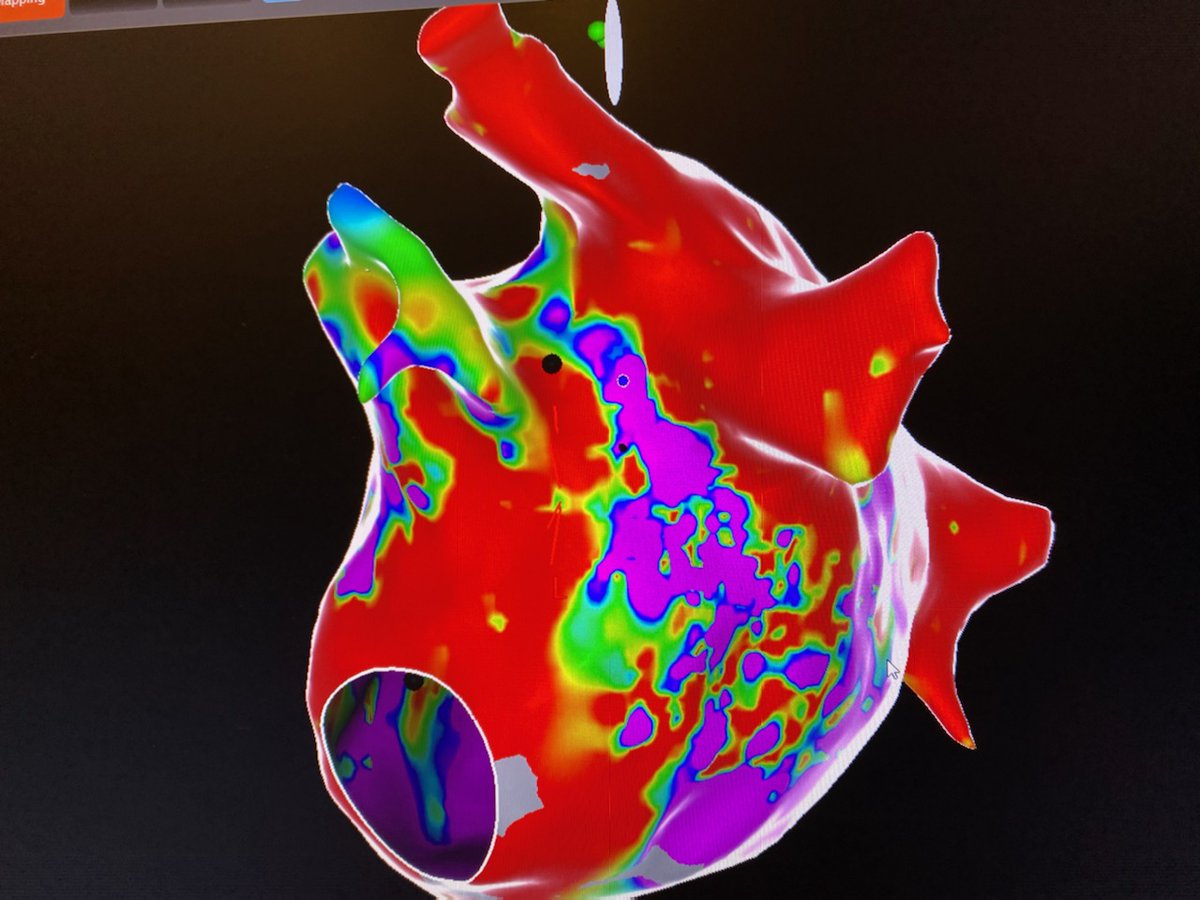

Difficult mitral isthmus line after mitral flutter induced post atrial fibrillation ablation. Intermittent block with multiple endocardial burns. Bidirectional block after VOM injection with dramatic increase in endocardial scar on right @VirtuaHealth @VirtuaHRS @AatishGarg_EP

Delighted to start the Vein of Marshall alcohol ablation program at @VirtuaHealth with @VirtuaHRS Grateful to @jaykoneru and @KennethEllenbo1 for their guidance along with @MiguelVldrbno and @EPbordeaux for their groundbreaking research articles.